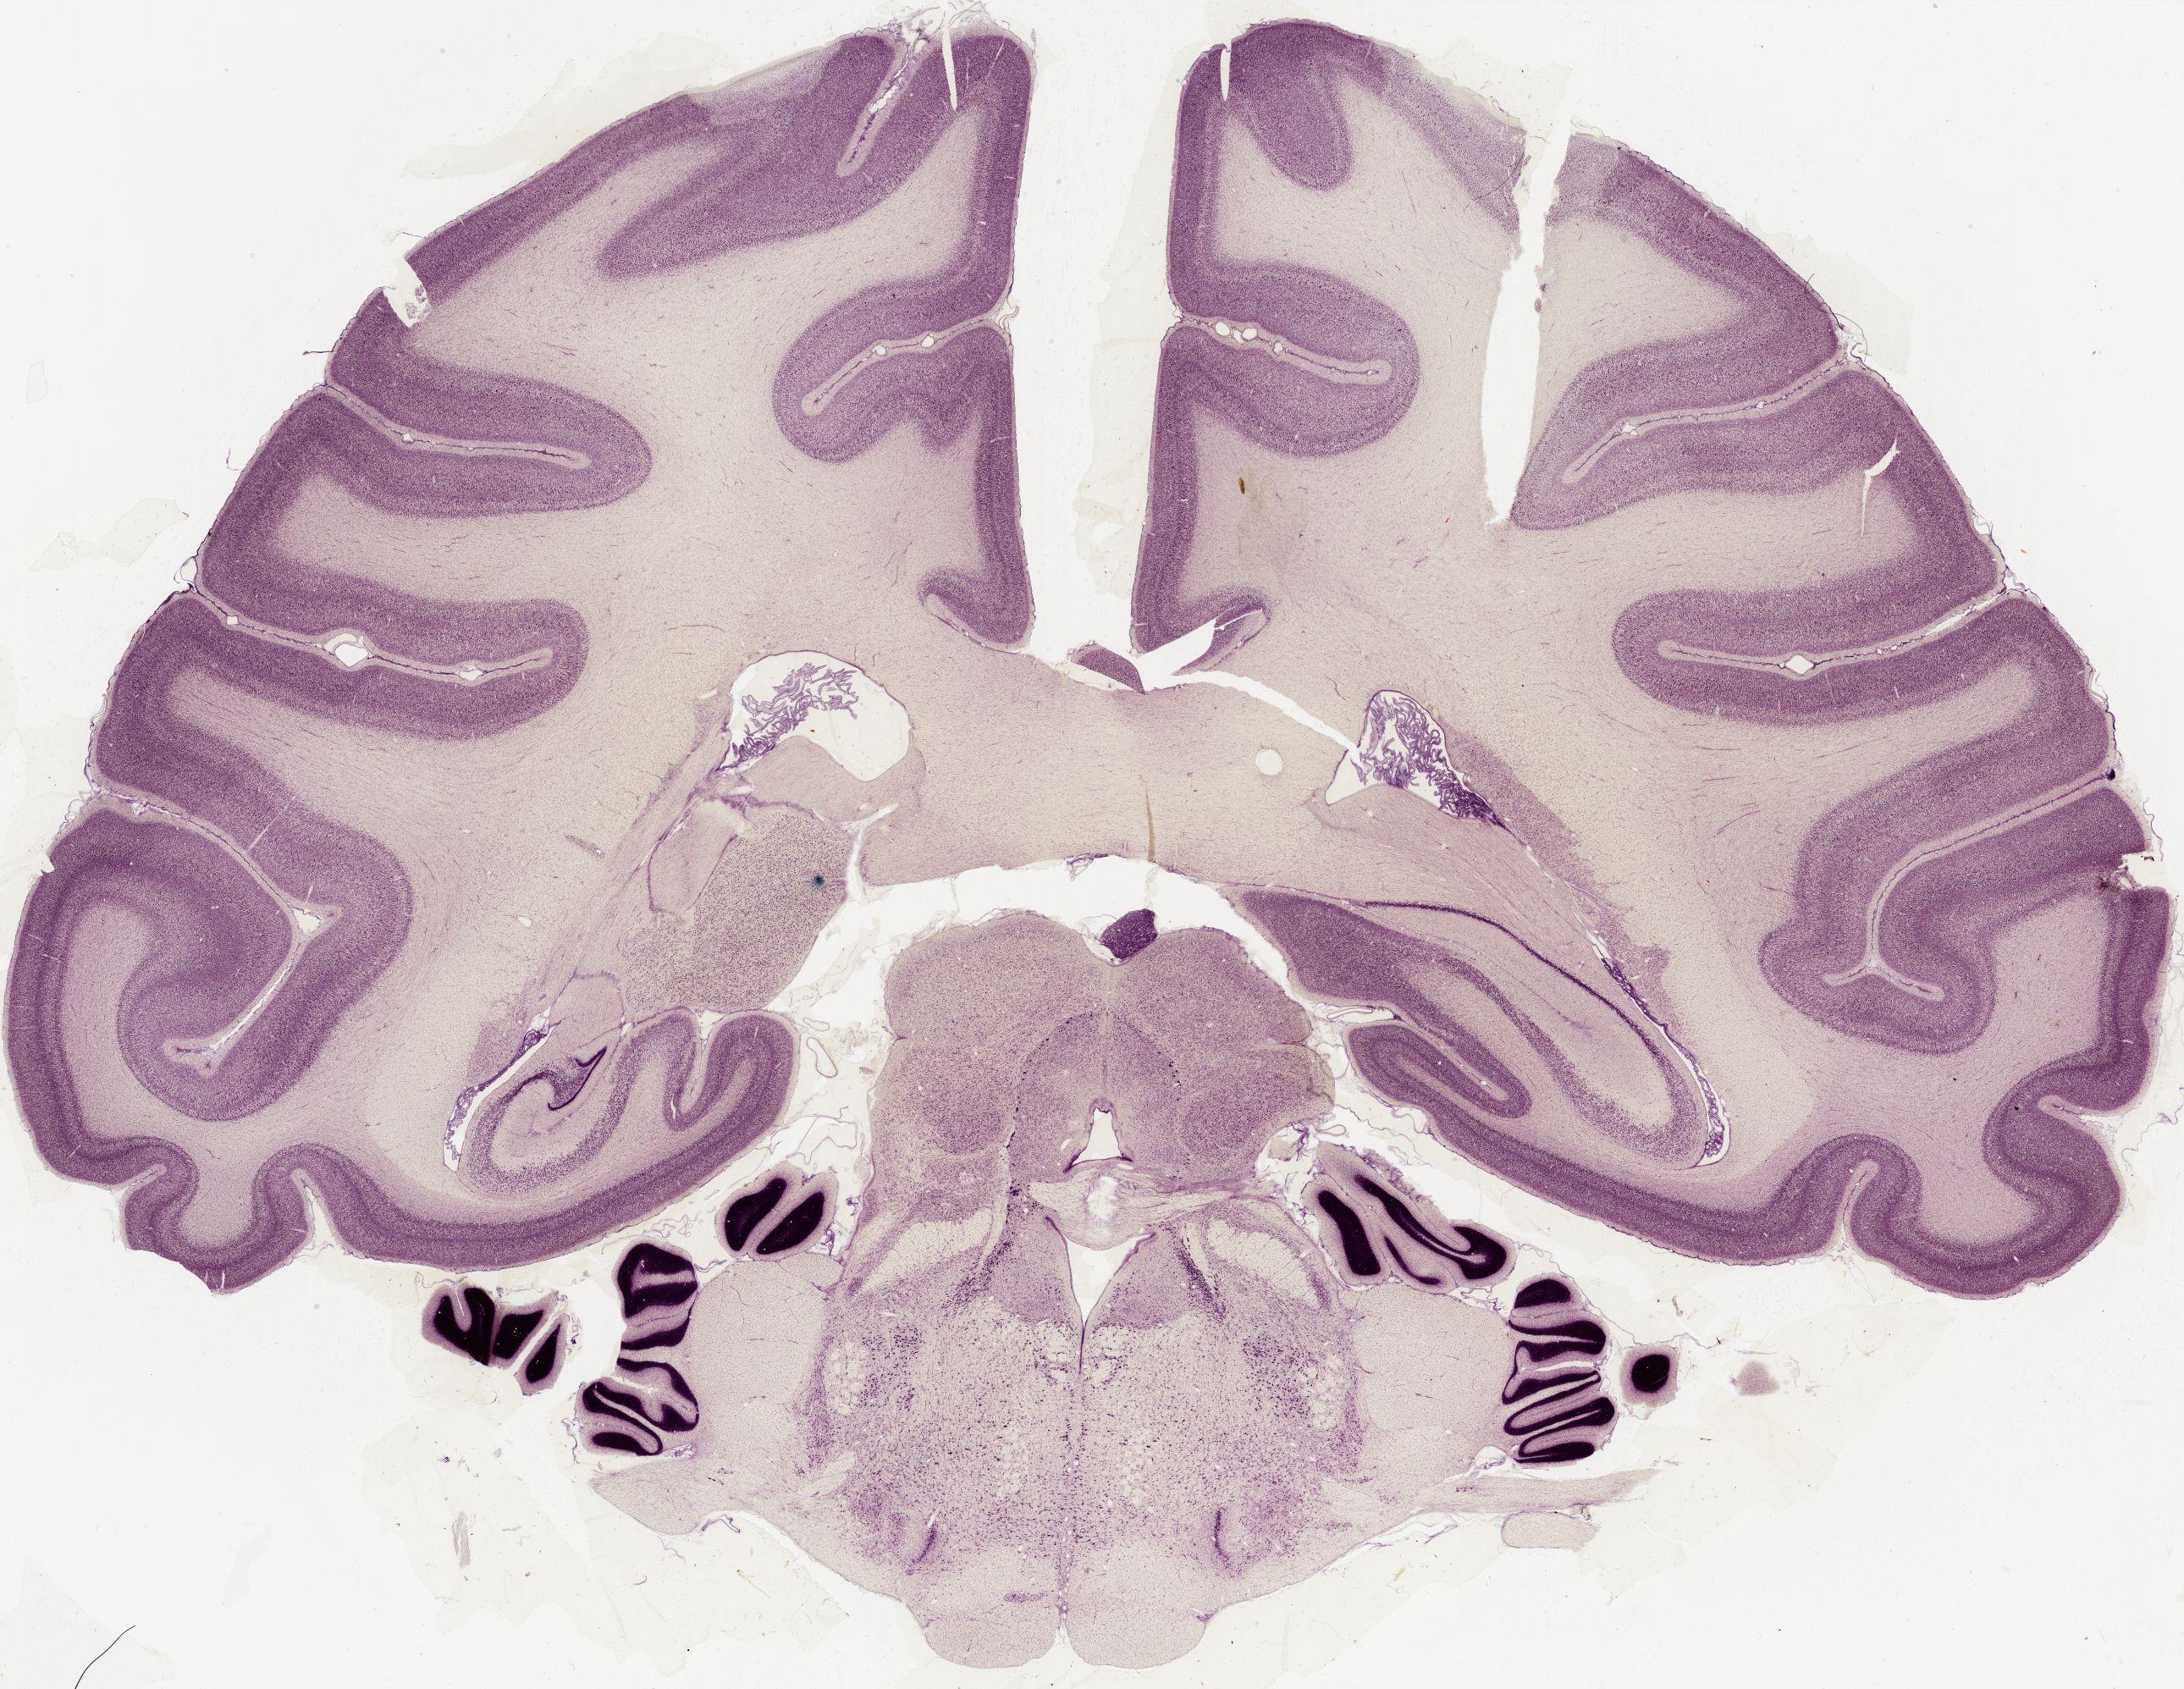

Datasets -> Macaca Mulatta -> Nissl, coronal, histo, Whole-Brain, adult

[ Metadata ]   ·   Source: Edward G. Jones

Displaying Sections 41 thru 56 of 56 Sections for this Dataset

0601 - labeled